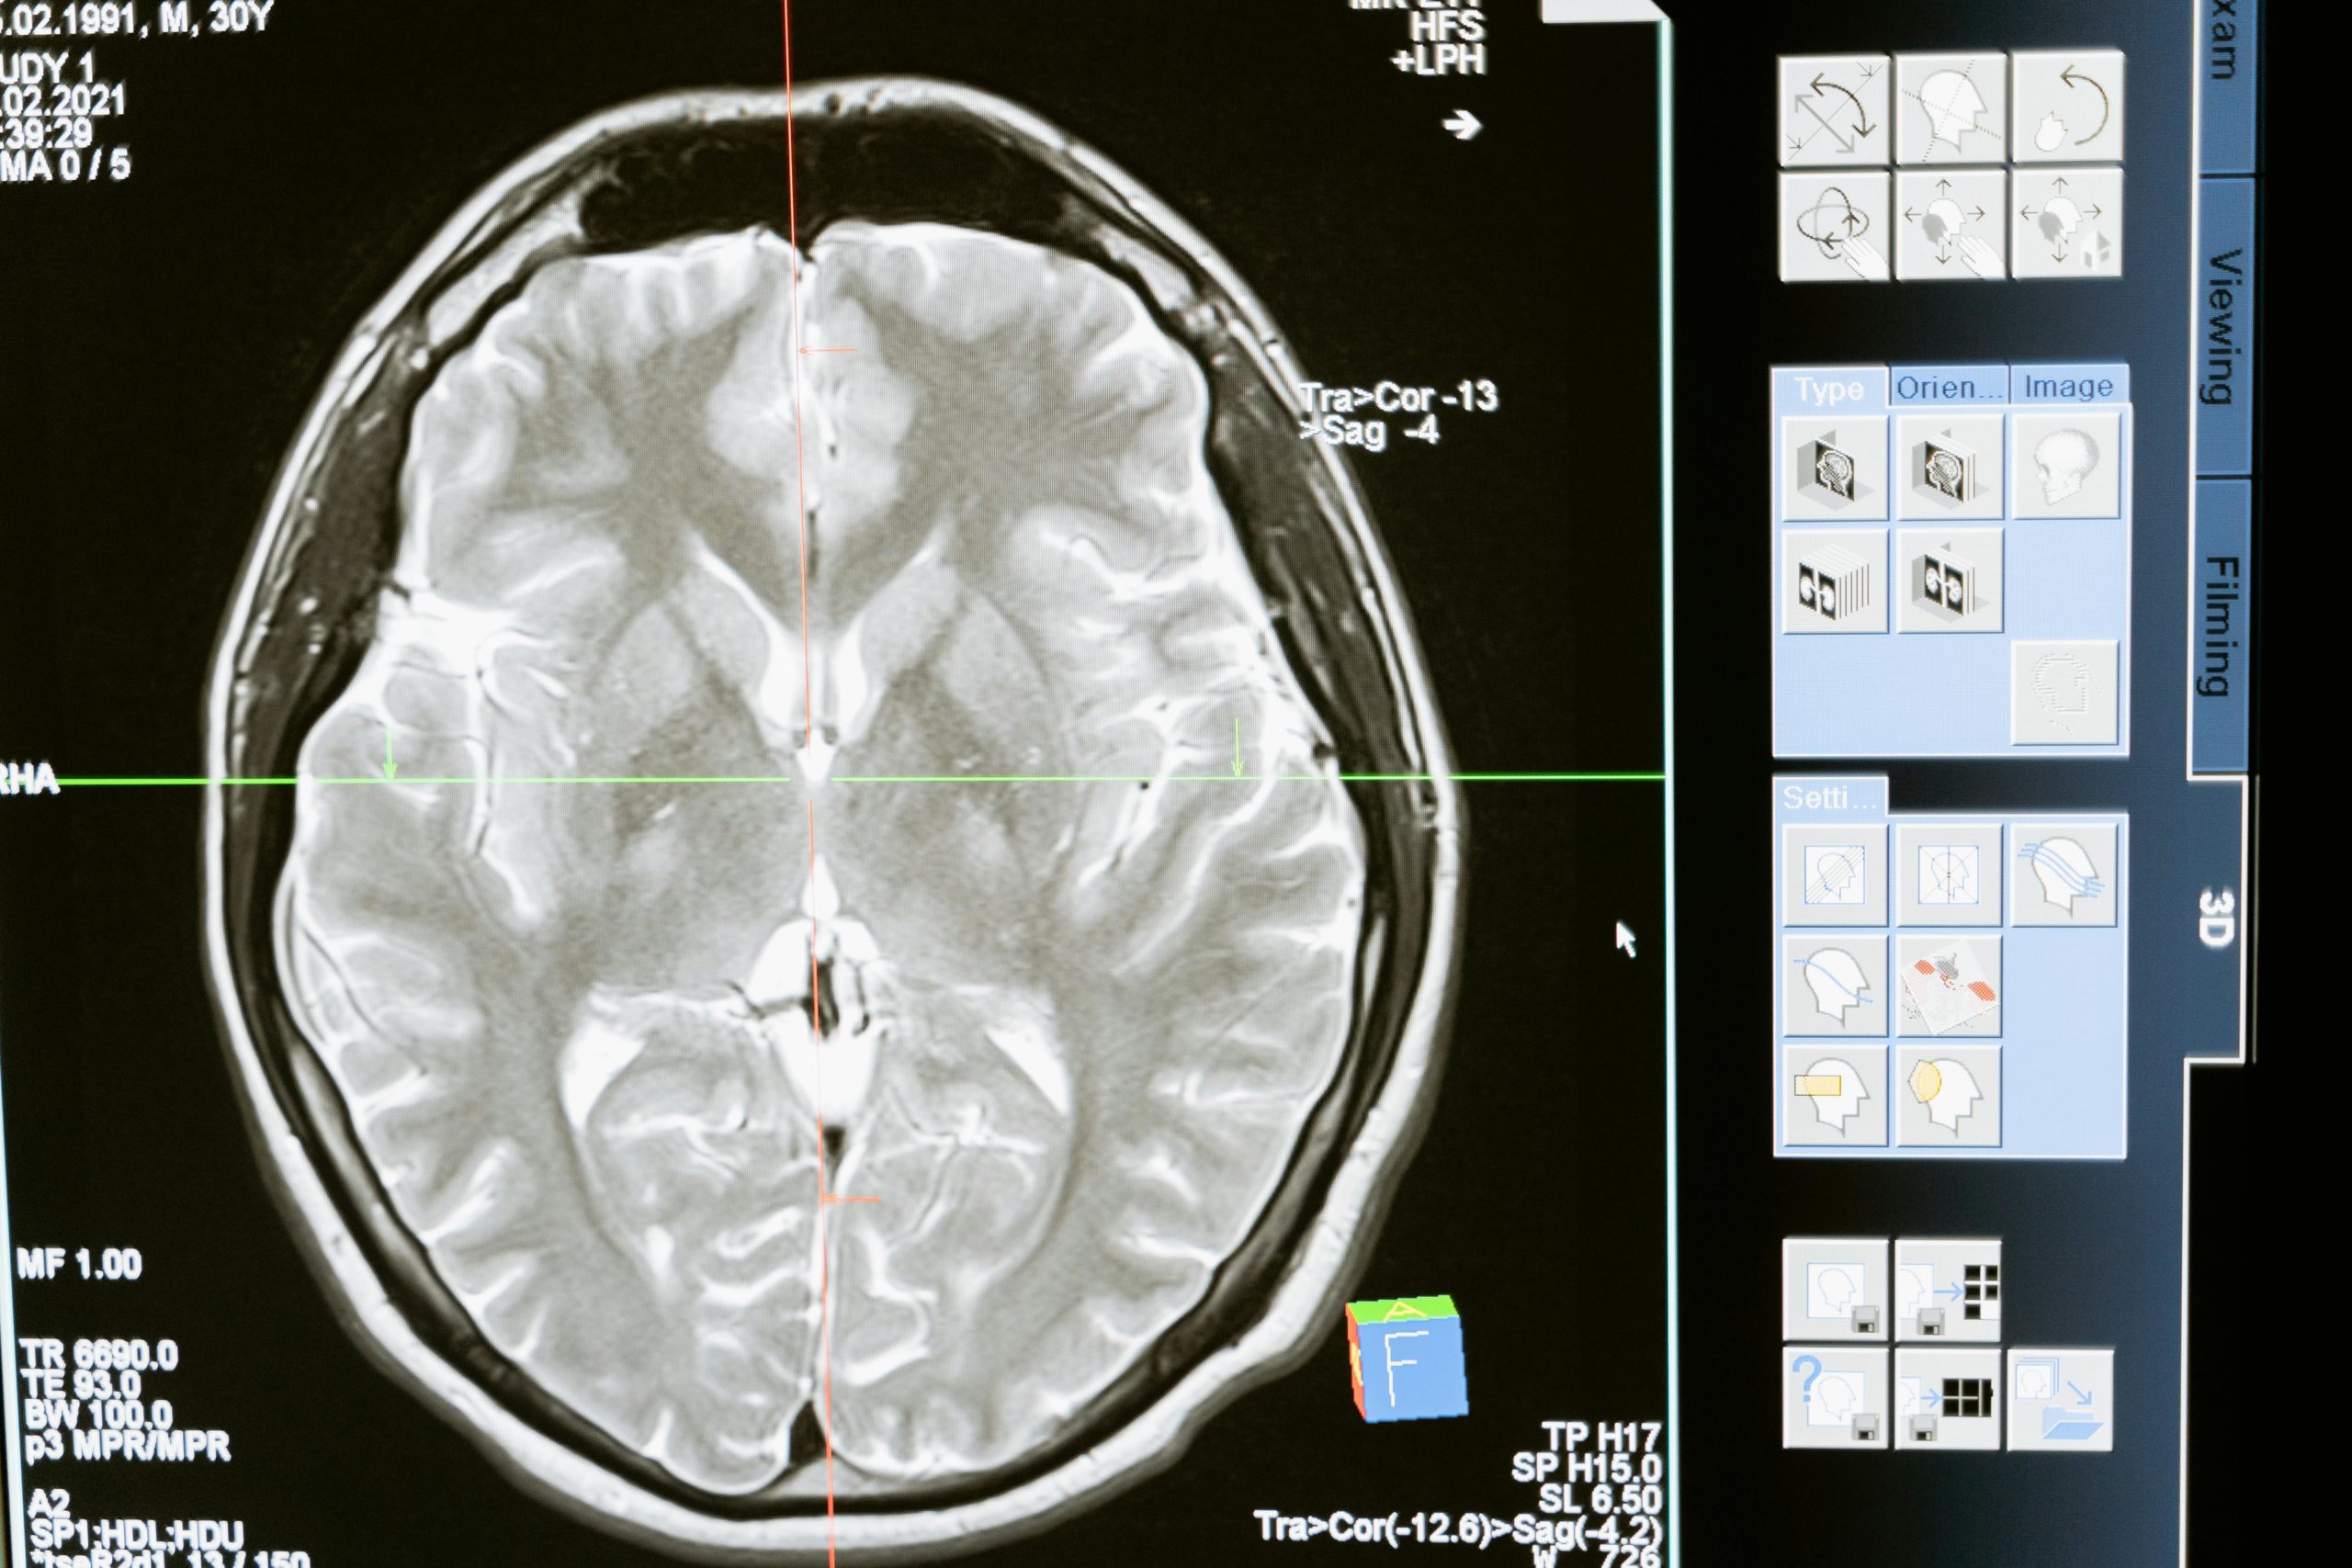

Gehirnforscher nutzen verschiedene Methoden, um im lebenden Menschen Einsicht in die Hirnaktivität zu gewinnen. Die wichtigsten Verfahren sind bildgebende Neuroimaging-Methoden und das EEG.

• MRT (Magnetresonanztomografie): Mit dem MRT können Forscher die Struktur und teilweise auch die Aktivität des Gehirns messen. Normale MRT-Bilder zeigen z. B. das Volumen von Hirnarealen oder bestimmen, ob die Anatomie normal ist. In der Lernforschung verwendet man vor allem das fMRT (funktionelle MRT). Dabei bleibt die Person in einer Röhre liegen und löst Aufgaben, während das Gerät Blutfluss und Sauerstoffverbrauch misst. Aktive Hirnregionen „leuchten“ dadurch in den Bildern auf.

Diese Forschungsmethoden haben bereits viele Überraschungen geliefert. So fanden Hirnforscher heraus, dass beim Erlernen eines Instruments wie Geige bestimmte Hirnareale wachsen oder stärker verknüpft werden. Eine Grundaussage lautet: Lernen verändert das Gehirn – und mit diesen Methoden können Wissenschaftler diese Veränderungen sichtbar machen.